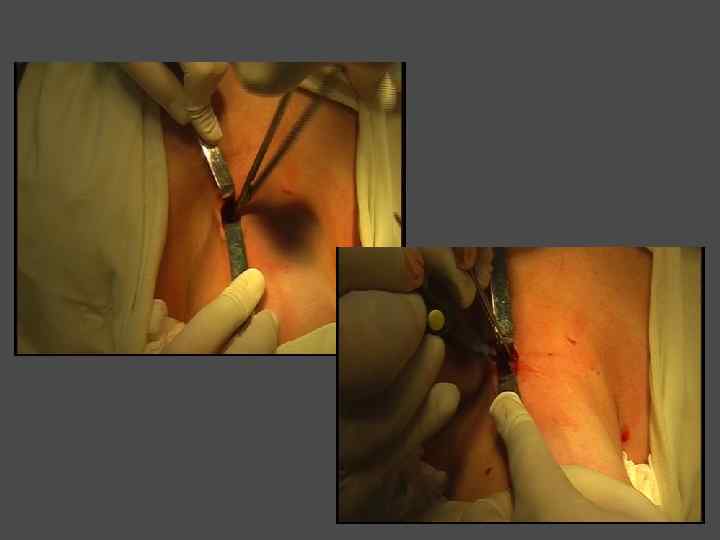

ЧРЕСКОЖНАЯ СКЛЕРОЗИРУЮЩАЯ ТЕРАПИЯ ЭТАНОЛОМ

ПОКАЗАНИЯ I. Показания, те же, что и к хирургическому лечению + ► Сопутствующая патология, исключающая возможность хирургического лечения. ► Категорический отказ больного от хирургического лечения. II. Солитарный (единичный) узел небольшого размера (<3 см)

ОБЯЗАТЕЛЬНОЕ УСЛОВИЕ ► Доброкачественный характер узлового образования Всем больным проводится пункционная тонкоигольная аспирационная биопсия под контролем УЗИ

ЭТАПЫ ЭТАНОЛОВОЙ ДЕСТРУКЦИИ УЗЛА БОЛЬШОГО ОБЪЕМА